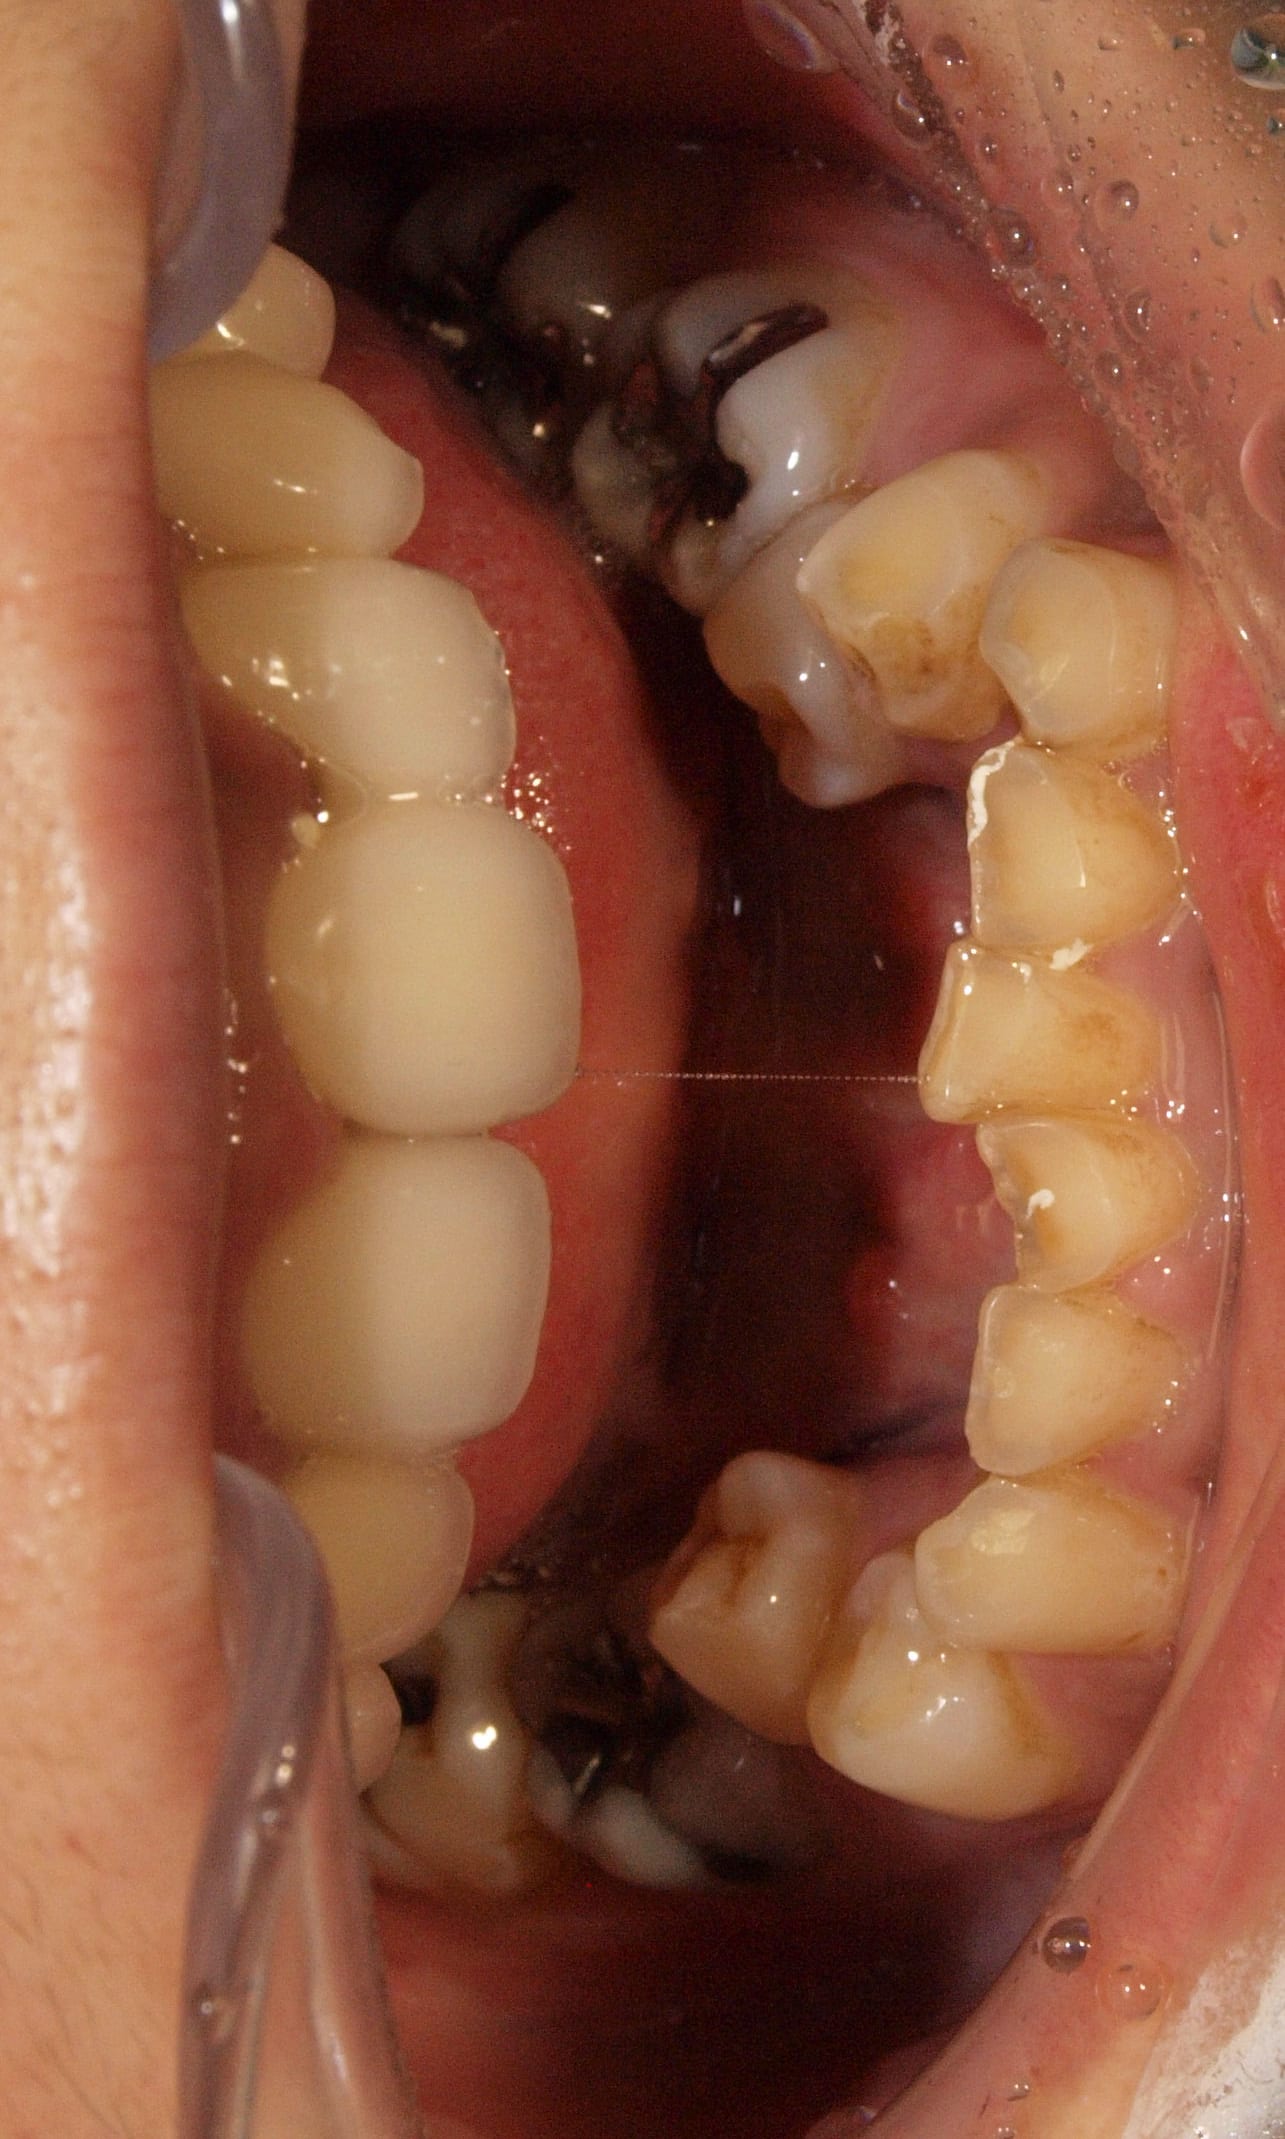

Voici une photo des incisives mandibulaires.

Assez abrasees en effet.

Dans le cas ou deux implants 23-24 seraient posés, vous y croyez vous que 21/22 tiendraient sans se decoller avec un tel over bite?

- Oui ? alors va falloir réfléchir à reprendre sérieusement le bas ça freine grave de l'avant qu'elle va finir en OTB (déformation passionnelle).

Pour moi c'est un cas orthodontique avec +/- chir ortho...